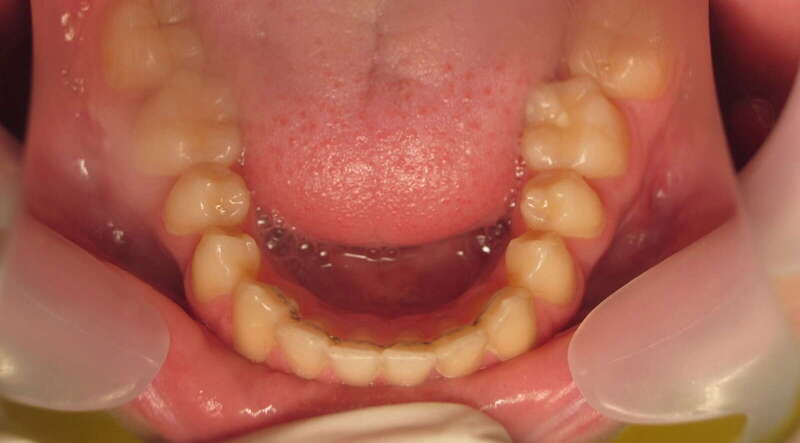

Cas n°1 traité par aligneurs (interception) - enfant

Ce cas d’interception chez un enfant de 8 ans démontre l'efficacité des aligneurs pour corriger des troubles fonctionnels précoces. Le diagnostic présentait des inversions d'articulé provoquant une déviation de la mandibule vers la gauche et un décalage des milieux.

Grâce à une coopération exemplaire et un traitement totalement indolore, l'expansion de l'arcade a permis de recentrer la mâchoire. Cette intervention a littéralement remis la croissance sur les rails, neutralisant le risque d'asymétrie faciale squelettique.

• Correction fonctionnelle : Recentrage immédiat de la mandibule et des milieux inter-incisifs.

• Prévention : Création d'un environnement favorable pour les dents définitives à venir.

• Bien-être : Approche douce respectant le confort de l'enfant.

C'est une étape fondamentale qui simplifie l'avenir orthodontique du patient tout en garantissant un développement facial harmonieux.